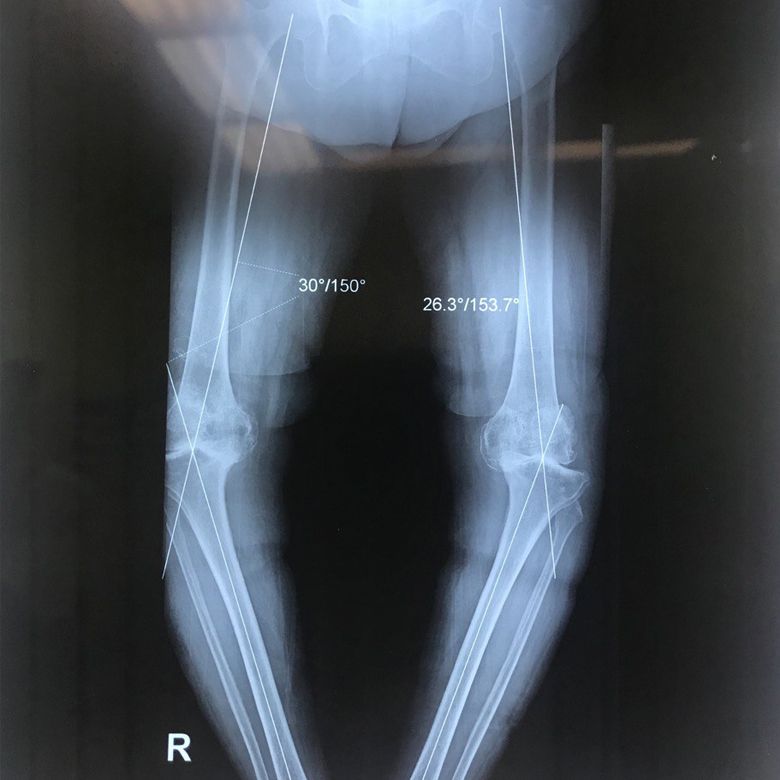

Dizde eksenel sapma

Diz aksiyel deviasyonu dizin yapısal bozukluklarından biri olup, dizde parantez veya çaprazlama şeklinde görülebilir.